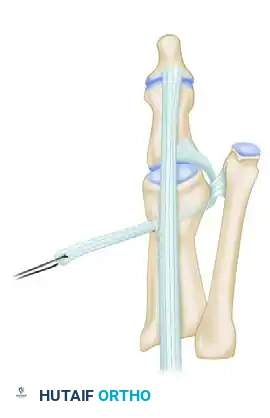

CORRECTION OF DYNAMIC (MULTIPLANAR) HALLUX VARUS Surgical Diagram

The transected EHB tendon is passed deep to the transverse metatarsal ligament from distal to proximal, utilizing the ligament as a biomechanical pulley.